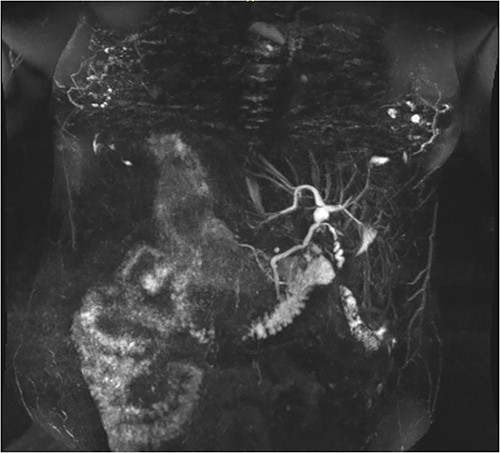

Following examination, a magnetic resonance cholangiopancreatography (MRCP) test was requested to exclude choledocholithiasis. 24 hours later, this confirmed gallstones, with 10 mm saccular dilatations near the hilar confluence (Figs 1 and 2). This dilatation was non-progressive according to previous scans, with unaffected pancreatic and intrahepatic ducts. Dilated portal vessels and varices were discovered to be directly communicating with the gallbladder fossa, suggestive of portal venous communication.

Axial MRCP scan demonstrating small stones in a contracted gallbladder.

Coronal MRCP scan demonstrating a 10 mm area of saccular duct dilatation at the hilar confluence. Large, dilated vessels/varices surrounding the gallbladder fossa can also be appreciated.